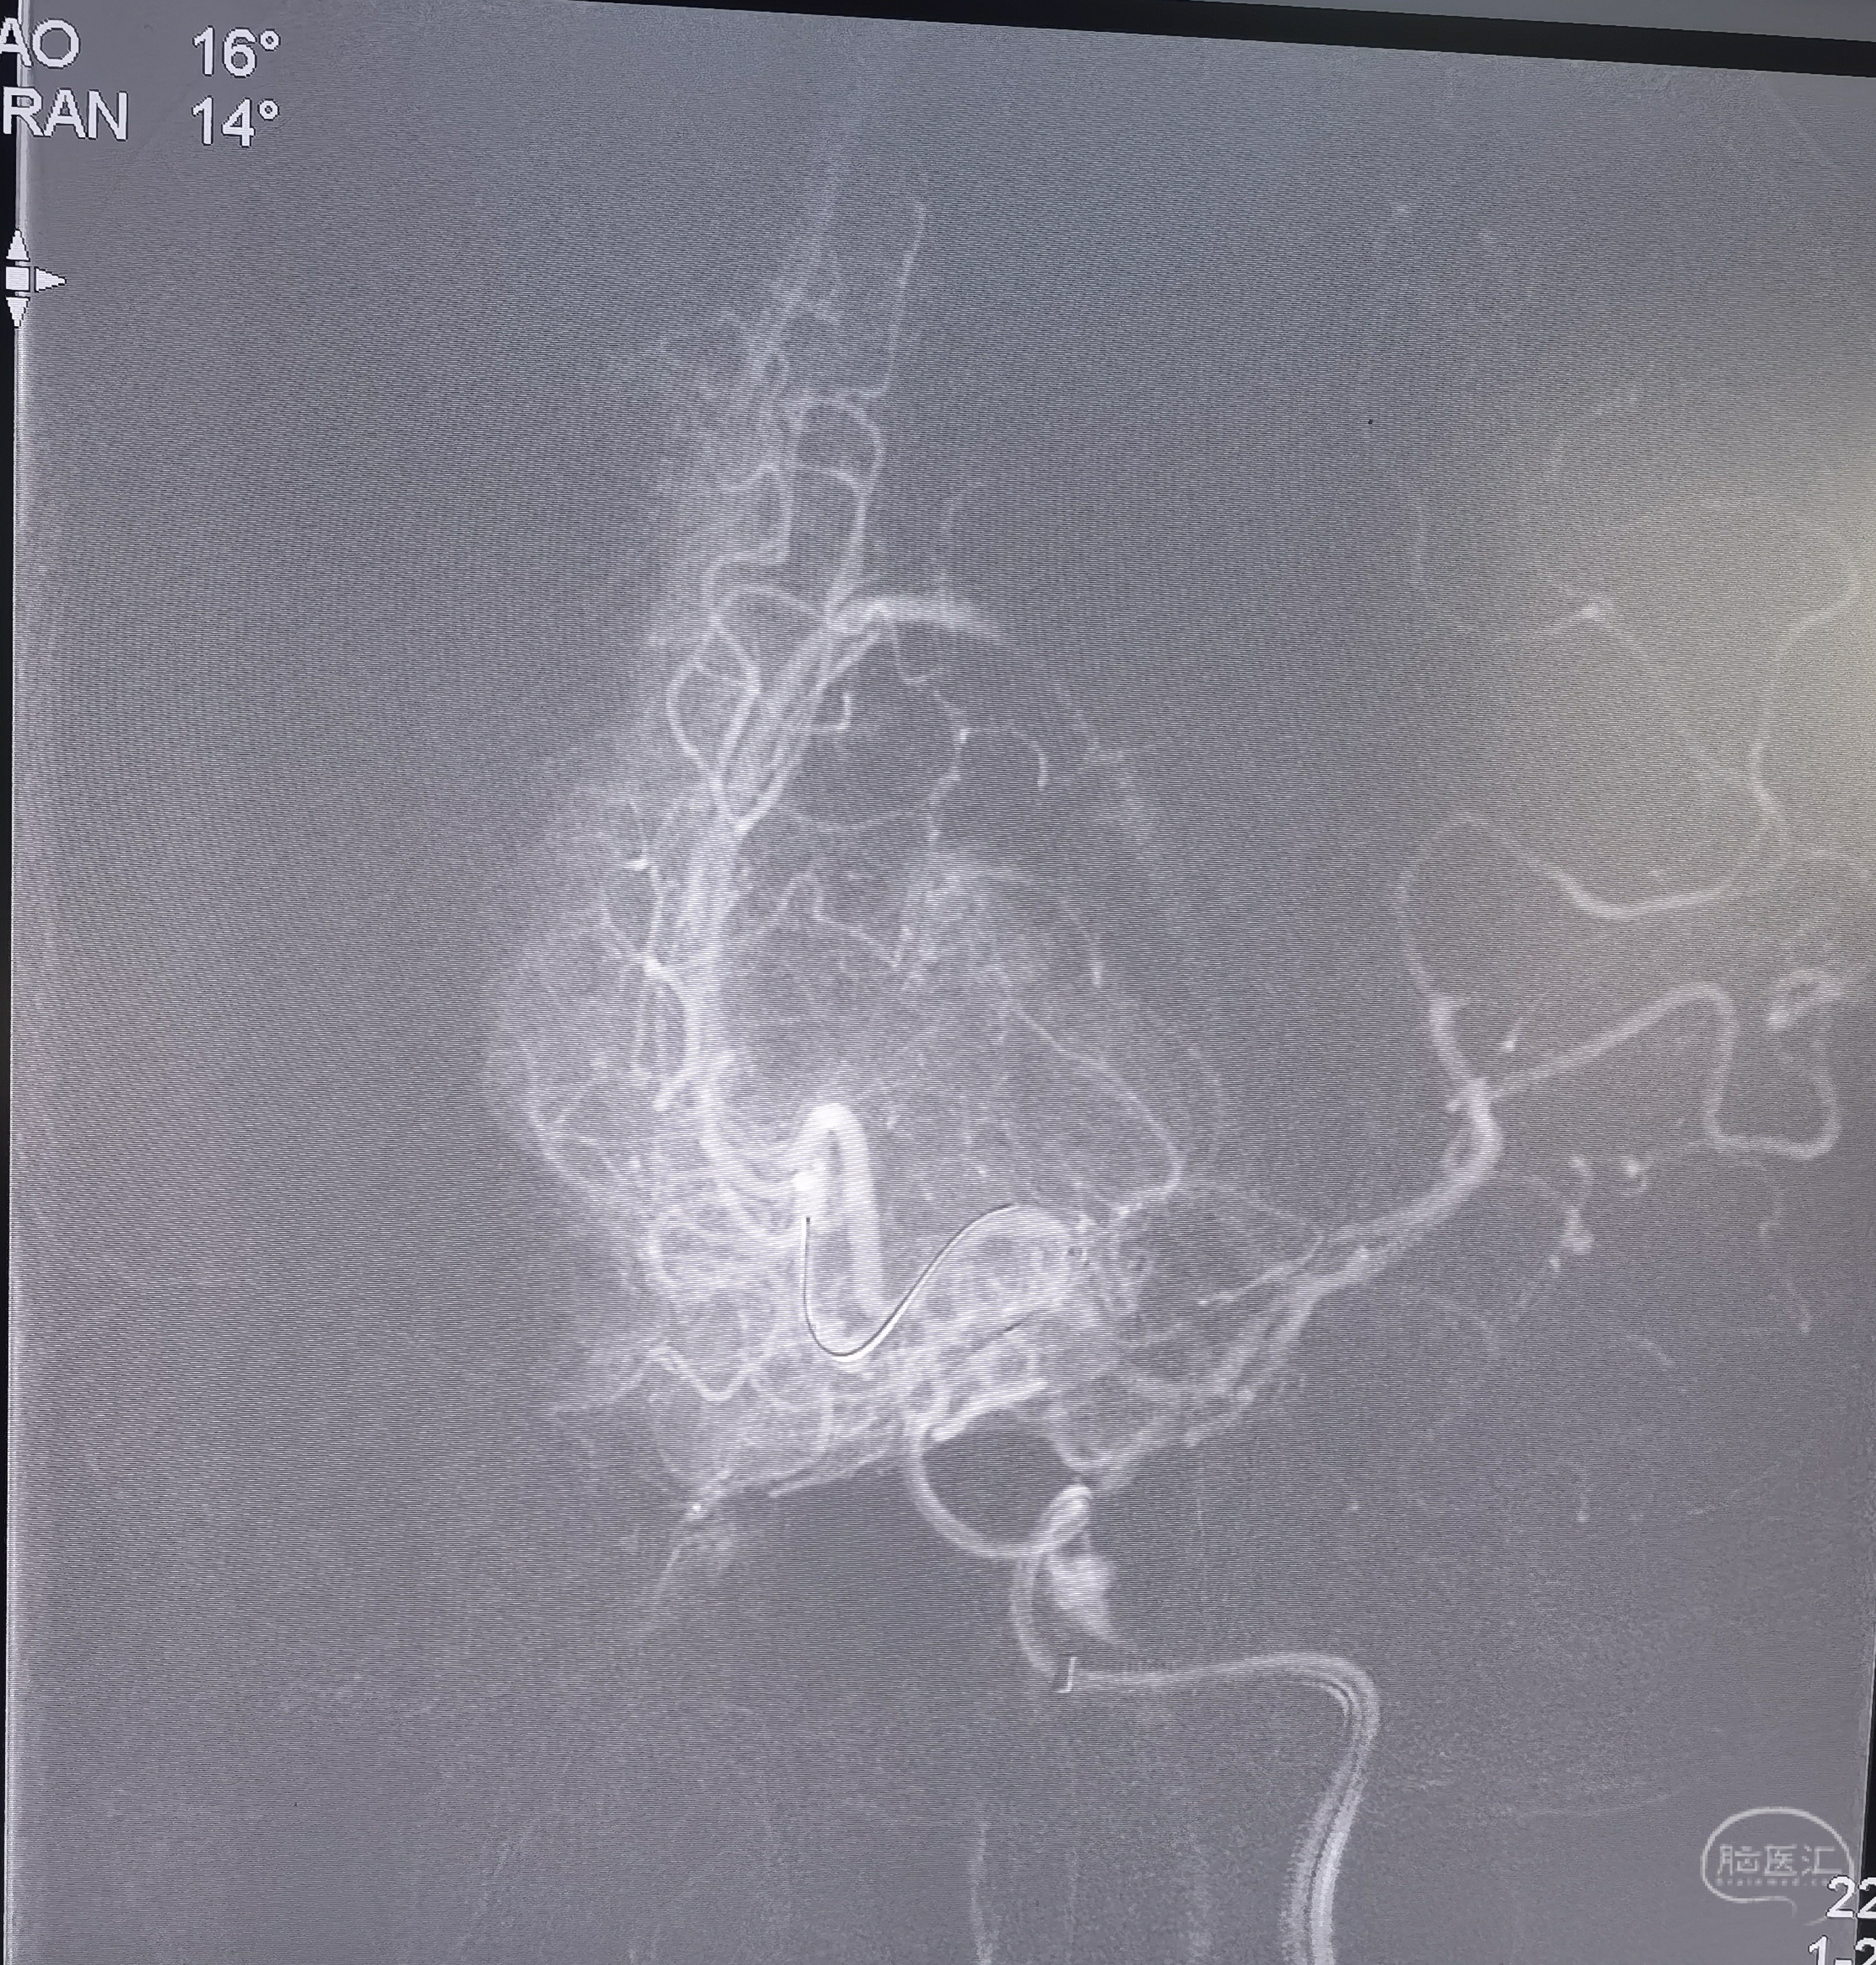

颈内动脉起始段重度狭窄

支架置入

支架置入后造影侧位

支架置入后造影正位